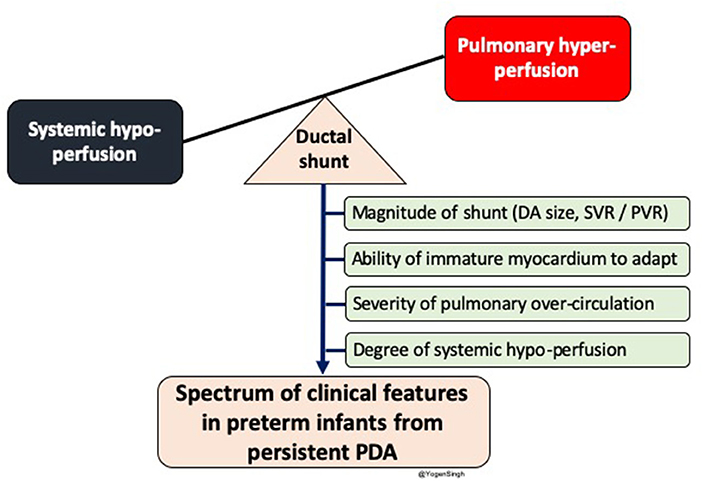

The clinical signs of PDA depend upon amount of the shunt volume passing across the ductus arteriosus; which primarily depends upon the systemic and pulmonary vascular resistance, ability of the myocardium to adapt to increased shunt volume and size of the ductus arteriosus (13–15) (Figure 1).

Figure 1. Diagram showing impact of significant left to right shunt across ductal arteriosus (DA) leading to pulmonary over-circulation and systemic hypoperfusion. Spectrum of clinical features in preterm infants depends upon magnitude of ductal shunt, which depends upon DA size and balance between systemic and pulmonary vascular resistance, and inability of immature myocardium to adpat to circulatory disturbance. PDA, patent ductus arteriosus; SVR, systemic vascular resistance; PVR, pulmonary vascular resistance.